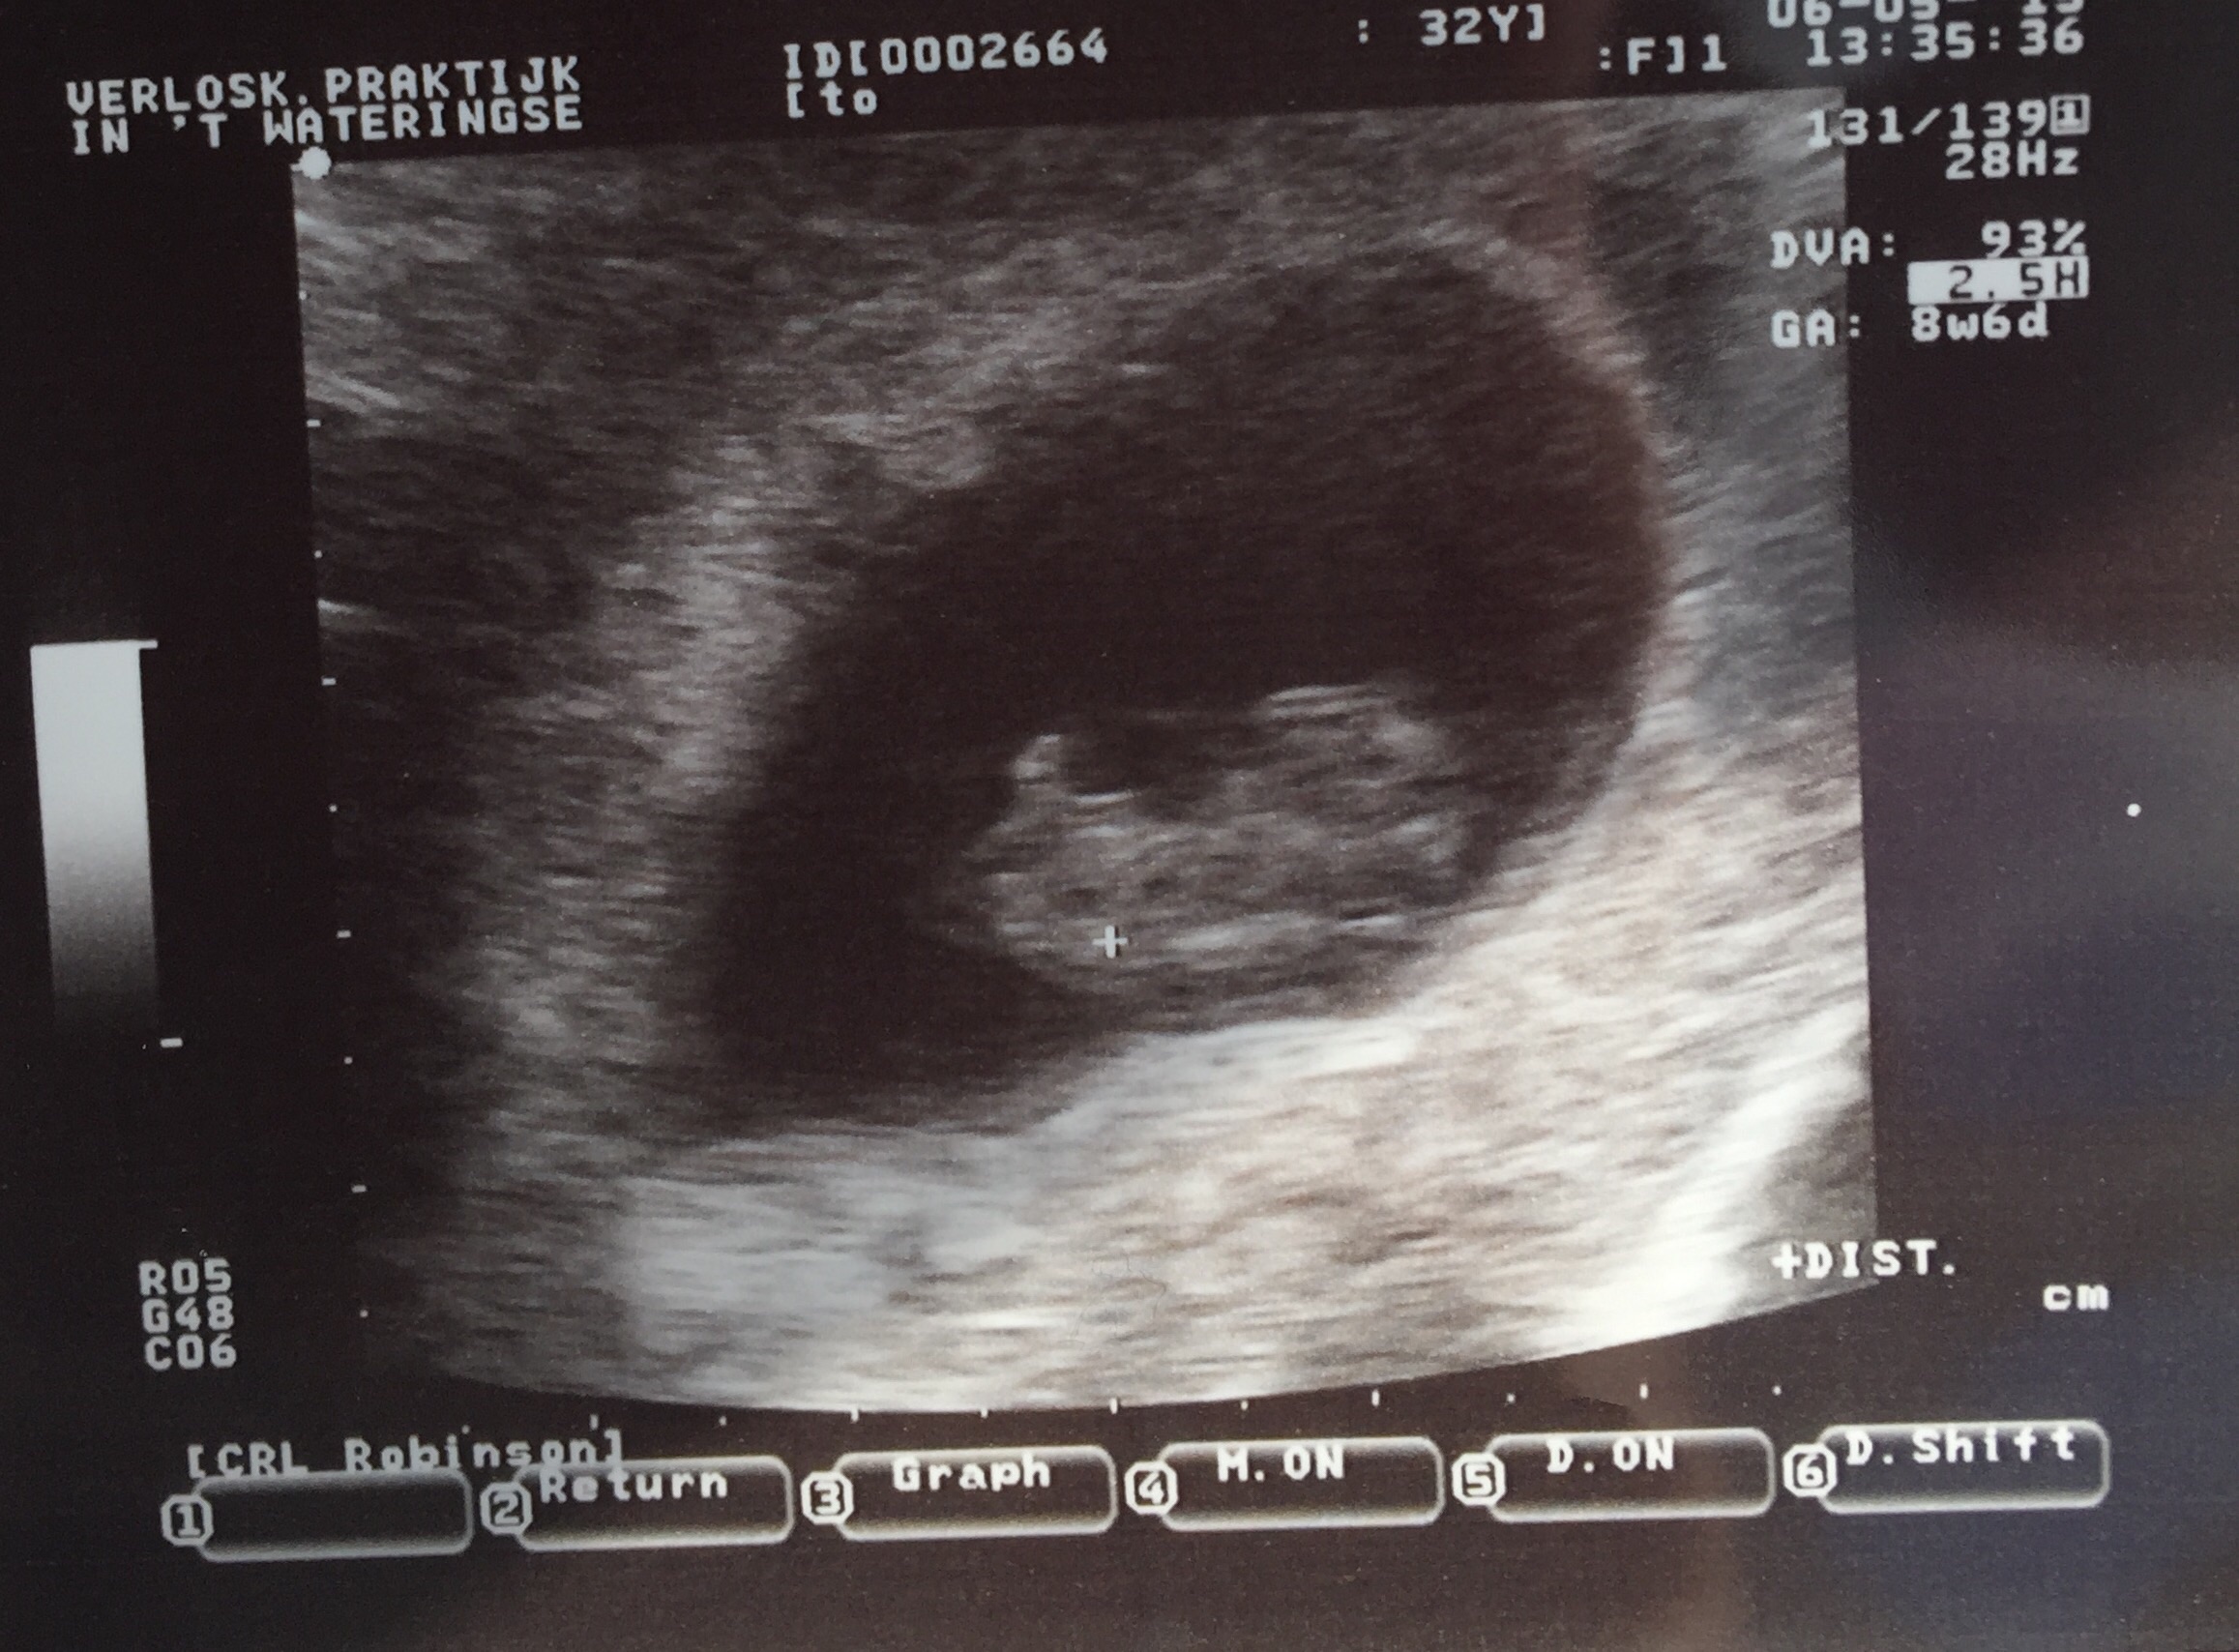

Taken at 8w6d but measuring 8w3d for now. We saw the heart flickering and the baby was waiving arms!! Cute Cute Cute, so happy! I go back in 3 weeks for another one.